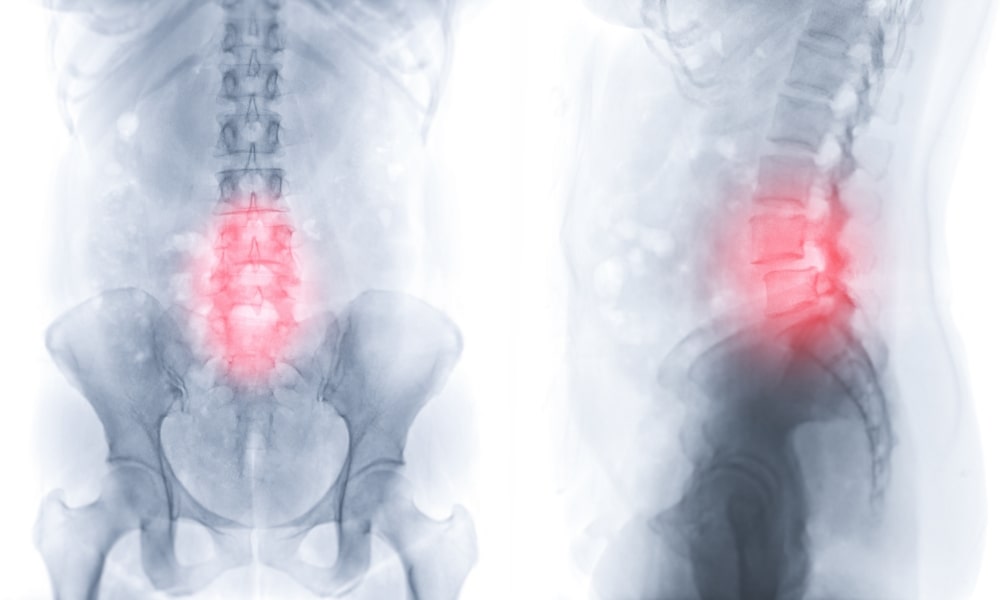

ぎっくり腰とは、正式には急性腰痛症と呼ばれ、突発的に腰部に激しい痛みが走る症状の総称です。

特定の疾患名ではなく、あくまで症状を表す言葉であり、様々な原因によって引き起こされます。

痛みの程度は非常に強く、軽度のものでは「動きにくい」程度ですが、重度の場合は「全く動けない」「寝返りも打てない」といった状態になることも珍しくありません。ぎっくり腰がきっかけで椎間板ヘルニアを発症する人もいるくらいです。